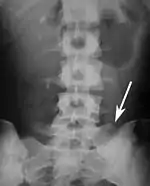

The fifth lumbar vertebra is characterized by its body being much deeper in front than behind, which accords with the prominence of the sacrovertebral articulation; by the smaller size of its spinous process; by the wide interval between the inferior articular processes, and by the thickness of its transverse processes, which spring from the body as well as from the pedicles.[1] The fifth lumbar vertebra is by far the most common site of spondylolysis and spondylolisthesis.[3]

Most individuals have five lumbar vertebrae, while some have four or six. Lumbar disorders that normally affect L5 will affect L4 or L6 in these latter individuals.